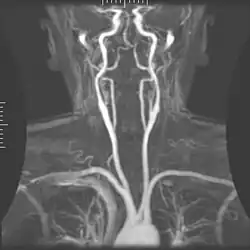

Angiografia

A angiografia por ressonância magnética (MRA) gera imagens das artérias para avaliá-las para estenose (estreitamento anormal) ou aneurismas (dilatação da parede vascular, em risco de ruptura). O MRA é frequentemente usado para avaliar as artérias do pescoço e do cérebro, a aorta torácica e abdominal, as artérias renais e as pernas (chamado de "escorrer"). Uma variedade de técnicas podem ser usadas para gerar as imagens, como a administração de um agente de contraste paramagnético (gadolínio) ou usando uma técnica conhecida como "aprimoramento relacionado ao fluxo" (por exemplo, sequências de tempo de voo 2D e 3D), onde a maior parte do sinal em uma imagem é devido ao sangue que recentemente se mudou para esse plano. As técnicas que envolvem acumulação de fase (conhecida como angiografia por contraste de fase) também podem ser usadas para gerar mapas de velocidade de fluxo com facilidade e precisão. A venografia por ressonância magnética (MRV) é um procedimento similar que é usado para imagens de veias. Neste método, o tecido agora está excitado inferiormente, enquanto o sinal é recolhido no plano imediatamente superior ao plano de excitação - criando assim o sangue venoso que recentemente se moveu do plano excitado.[52]